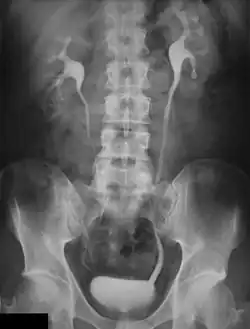

Urografía

La urografía es un examen radiográfico de contraste, que consiste en la realización de radiografías seriadas para ilustrar el paso de contraste previamente administrado por vía intravenosa.[1] El contraste permite la exploración y el estudio de diversas secciones de las vías urinarias y detectar alteraciones en la secreción urinaria, desde el parénquima renal hasta la vejiga.

El estudio se basa en visualizar la excreción renal con el paso de los medios de contraste yodados que logran oscurecer la orina y, por tanto, hacer visibles las cavidades naturales de las vías urinarias: los conductos colectores del riñón, uréter y vejiga urinaria. La urografía permite la exploración morfológica y funcional de estos .

Después de inyectar un medio de contraste a base de yodo en la vena, la urografía permite ver y estudiar las diferentes secciones del tránsito de excreción de la orina: cálices y ampolla renales, los uréteres y la vejiga.[1] De cada una de estas secciones se evaluará el tipo, la ubicación, el tamaño, el curso (en el caso de los uréteres) y la apriencia de las paredes tubulares. Además de estos hallazgos morfológicos, se pueden demostrar hallazgos funcionales, tales como apariencia, la durabilidad y la simetría de la eliminación, la intensidad y homogeneidad de la opacidad y la motilidad de las diversas secciones (la pelvis renal, uréteres y vejiga).

Los medios de contraste utilizados son compuestos orgánicos a base de triodo, solubles en agua los que se inyectan por vía intravenosa o por infusión lenta. Después de la inyección de contraste se hacen radiografías seriados:[2]

- los primeros 2-3 minutos de la inyección: es la placa radiológica funcional de la urografía;

- los siguientes 10-15 minutos, y 30-45 minutos de la infusión intravenosa, y más tarde en algunos casos: son las placas morfológicas de la urografía.

Una encuesta realizada correctamente debe permitir la exploración y el estudio de los riñones, cálices renales, uréteres y vejiga. Este último debe ser considerado cuando complete el llenado y, posteriormente, después de la micción del contraste. En la sospecha de la ptosis renal, debe ejecutarse una radiografía en posición vertical, lo que permite una documentación más precisa sobre la localización del riñón.